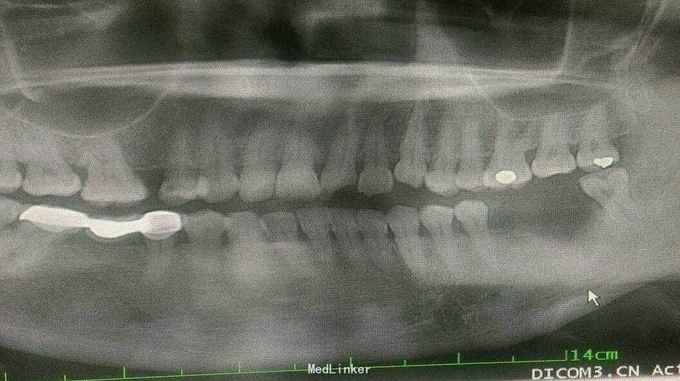

查体: 上下唇左侧有擦伤,痂皮已脱落。左侧口角处缝线已拆,触痛明显。牙齿检查,21-23牙冠折裂,其中21折断范围较大,远中切角缺如,最可喜的是,远中颊角及邻面处断面平龈,近远中邻接关系未破坏,牙髓暴露,叩痛明显。22,23切端折断,未露髓,暂无不适。 三牙牙体折断面已污染。 咬合关系检查,无明显高点,张口度可。 精神状态及依从性评估: 精神低落,极度敏感。一年前,家里发生变故,丈夫去世,一直睡眠质量较差。此次看牙,由新男友陪同,神情恍惚,不敢高声言语,但面部焦急不堪。经朋友介绍,来找我就医。说明病情,治疗、修复方案,知情同意。 辅查: 根尖片,21-23无根折,根尖区无阴影。

诊断: 21-23冠折,21急性牙髓炎 治疗修复方案: 21根管治疗,树脂修复。 步骤: 1,21局麻下拔髓,调咬合,初步急性处理。折断面暂不做任何处理。转治疗医生。 2,分层树脂修复21。 A,清洗断面,打磨锐利边缘,无基釉,砂纸、毛刷抛光粘结面。 B,比色。 C,隔湿,排龈,成型片隔离邻牙。 D,酸蚀,涂粘结剂。 E,分层树脂充填。硅橡胶舌侧树脂薄翼,简化操作难度,节省材料。 F,修形,抛光,涂偶联剂。 3,延期树脂修复22,23。